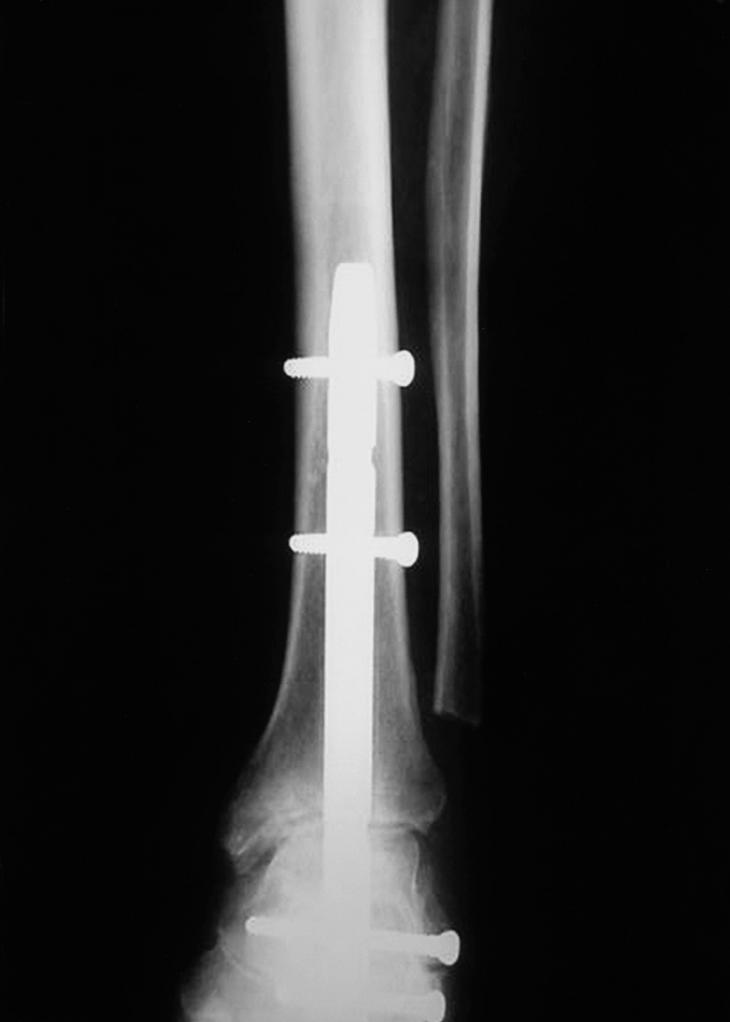

Rotura Tibia Y Peroné Operación Con Clavo Intramedular, , , , , , , 0, Tratamiento de fractura de tibia y perone en niños y adultos, www.fisioterapiaparatodos.com, 709 x 616, jpeg, WebFractura abierta de tibia y peroné. Se trata de una fractura en la que la piel está perforada y los huesos son visibles a través de la herida, y requiere una intervención. WebLa utilización de un clavo intramedular en caso de fracturas de tibia y peroné es para ayudar a que los huesos fracturas tengan un optimo proceso de consolidación, y para su retiro., 20, rotura-tibia-y-perone-operacion-con-clavo-intramedular, Novedades y Muebles WebFractura abierta de tibia y peroné. Se trata de una fractura en la que la piel está perforada y los huesos son visibles a través de la herida, y requiere una intervención. WebLa utilización de un clavo intramedular en caso de fracturas de tibia y peroné es para ayudar a que los huesos fracturas tengan un optimo proceso de consolidación, y para su retiro.

WebPues mira, yo llevo casi 9 meses de operado (tengo 2 clavos intramedulares de titanio, 8 tornilllos, tuve fractura de tibia, perone, femur, empeine y un dedo del pie. WebSi se utiliza un “clavo intramedular” para fijar la tibia rota (es el tipo de cirugía más común para una pierna rota), las personas suelen poder caminar con la pierna.

WebYo con rotura de tibia y peroné, me metieron un hierro intramedular en la Tibia con tornillos en la rodilla y abajo llegando al tobillo. Tarde casi 3 años en quitarlos y. WebProtocolo de rehabilitación de fracturas de tibia pdf. Se incluyeron 88 pacientes con 90 fracturas de tibia. Se utilizaron los siguientes criterios de inclusión: (1) pacientes adultos. WebLa fractura, como habíamos dicho más arriba, puede producirse en la tibia, en el peroné o en ambos huesos, y puede ser causada por un golpe, una caída, por un mecanismo de. WebAhora el turno de la tibia, en donde abren en la rodilla y meten el clavo intramedular, acomodandolo y fijandolo con sus tornillos. El perone, ya estaba. Webprotocolo de fisioterapia para clavos intramedulares en la tibia. ResumenEl enclavado intramedular con bloqueo estático y fresado sigue siendo el tratamiento estándar para. WebMe operaron y pusieron un clavo STRIKER 2 intramedular de tibia cpn dos tornillos sujetándolo, uno en tobillo y otro abajo de la rodilo; además de dos.

WebPARA LA FRACTURA DE LA TIBIA CON CLAVO INTRAMEDULAR ACTIVIDAD NO ASPOYE PESO en la pierna operada hasta que se lo permita el Dr. Gilmer. Por favor. WebUn clavo intramedular plantea la interferencia de la circulación intramedular y aunque la llegada de los vasos es fundamental en la reparación de las fracturas, los dos sistemas. WebMe fracturé tibia y peroné con desplazamientos hace 25 días. Durante los primeros 7 días llevé un yeso, después pasé por intervención donde se colocaron fijadores externos y a.

WebMe operaron y pusieron un clavo STRIKER 2 intramedular de tibia cpn dos tornillos sujetándolo, uno en tobillo y otro abajo de la rodilo; además de dos. WebHace 4 meses tuve fractura abierta de tibia y peroné, con operación para colocar clavo en la tibia, el peroné lo han dejado libre. Comencé con la fisioterapia al mes de operada para.